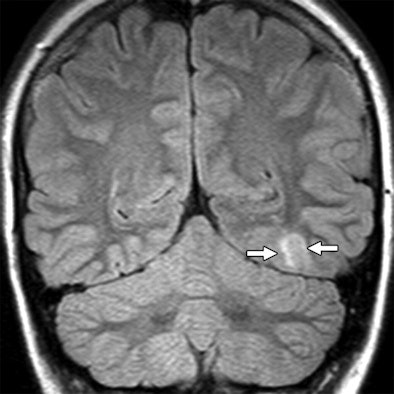

| Seventeen-year-old girl with intractable nocturnal seizures since the age of two. Above, coronal fluid-attenuated inversion recovery (FLAIR) 1.5-tesla MR image showing questionable curvilinear focus of juxtacortical high signal intensity (arrows) in left occipital lobe. Abnormal signal intensity was missed at first review of images. Below, coronal FLAIR 3-tesla MR image showing curvilinear band of high signal intensity (arrows) in left occipital juxtacortical white matter without apparent mass effect. Focus was surgically resected and histologic finding was focal cortical dysplasia with balloon cell features. |

| Images courtesy of the American Journal of Roentgenology and Oregon Health & Science University; from Phal P, Usmanov A, Nesbit G, et al. Qualitative comparison of 3-T and 1.5-T MRI in the evaluation of epilepsy. AJR. 2008;191:890-895. Figure 1. |